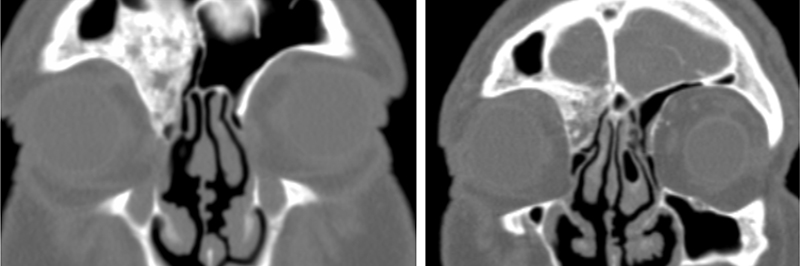

La determinación de hormonas tiroideas y anticuerpos anti-tiroides (anti-tiroglobulina y anti-peroxidasa) resultaron normales y negativos respectivamente. La tomografía computerizada (TC) de órbita no mostró engrosamiento ni asimetría de las dimensiones de los músculos extrínsecos oculares. Se observaron unas alteraciones en el ángulo superointerno del marco óseo de la órbita derecha (Figura 3a y Figura 3b) que involucraban múltiples huesos y se sugirió el diagnóstico de displasia fibrosa poliostótica. En la Tabla 2 se presentan las características clínicas y radiológicas de la displasia fibrosa y se incluyen otros trastornos con los que se establece el diagnóstico diferencial.

Figura 3a. TC órbita: Lesión en el ángulo superointerno de la órbita derecha con zonas hipodensas moteadas, con posible crecimiento intracraneal. Destaca a nivel del hueso frontal derecho, un engrosamiento óseo que ocupa parte del seno frontal ipsilateral y celdillas etmoidales anteriores derechas. En su interior se identifican zonas de esclerosis. Deforma discretamente el techo de la órbita derecha.